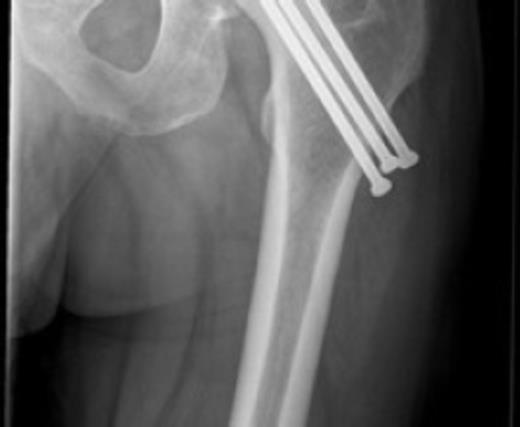

Postoperative care included early-supervised non-weight bearing mobilization for three months. Radiographs at three months showed no early displacement or evidence of avascular necrosis (Fig. 4). The patient progressed to protected full-weight bearing for a further three months.

At one year the patient was walking with a stick and mild limp, he had ninety degrees of hip flexion with limited internal and external rotation. Plain radiographs at this stage confirmed the fracture to be united with no evidence of avascular necrosis. The patient remained on yearly review and continued to function well. He returned to hobbies such as fishing and shooting and was pain free at three and a half years. The most recent review at four and a half years confirmed the presence of avascular necrosis (Fig. 5) however from a symptomatic point of view he is still able to maintain an active lifestyle with little pain.